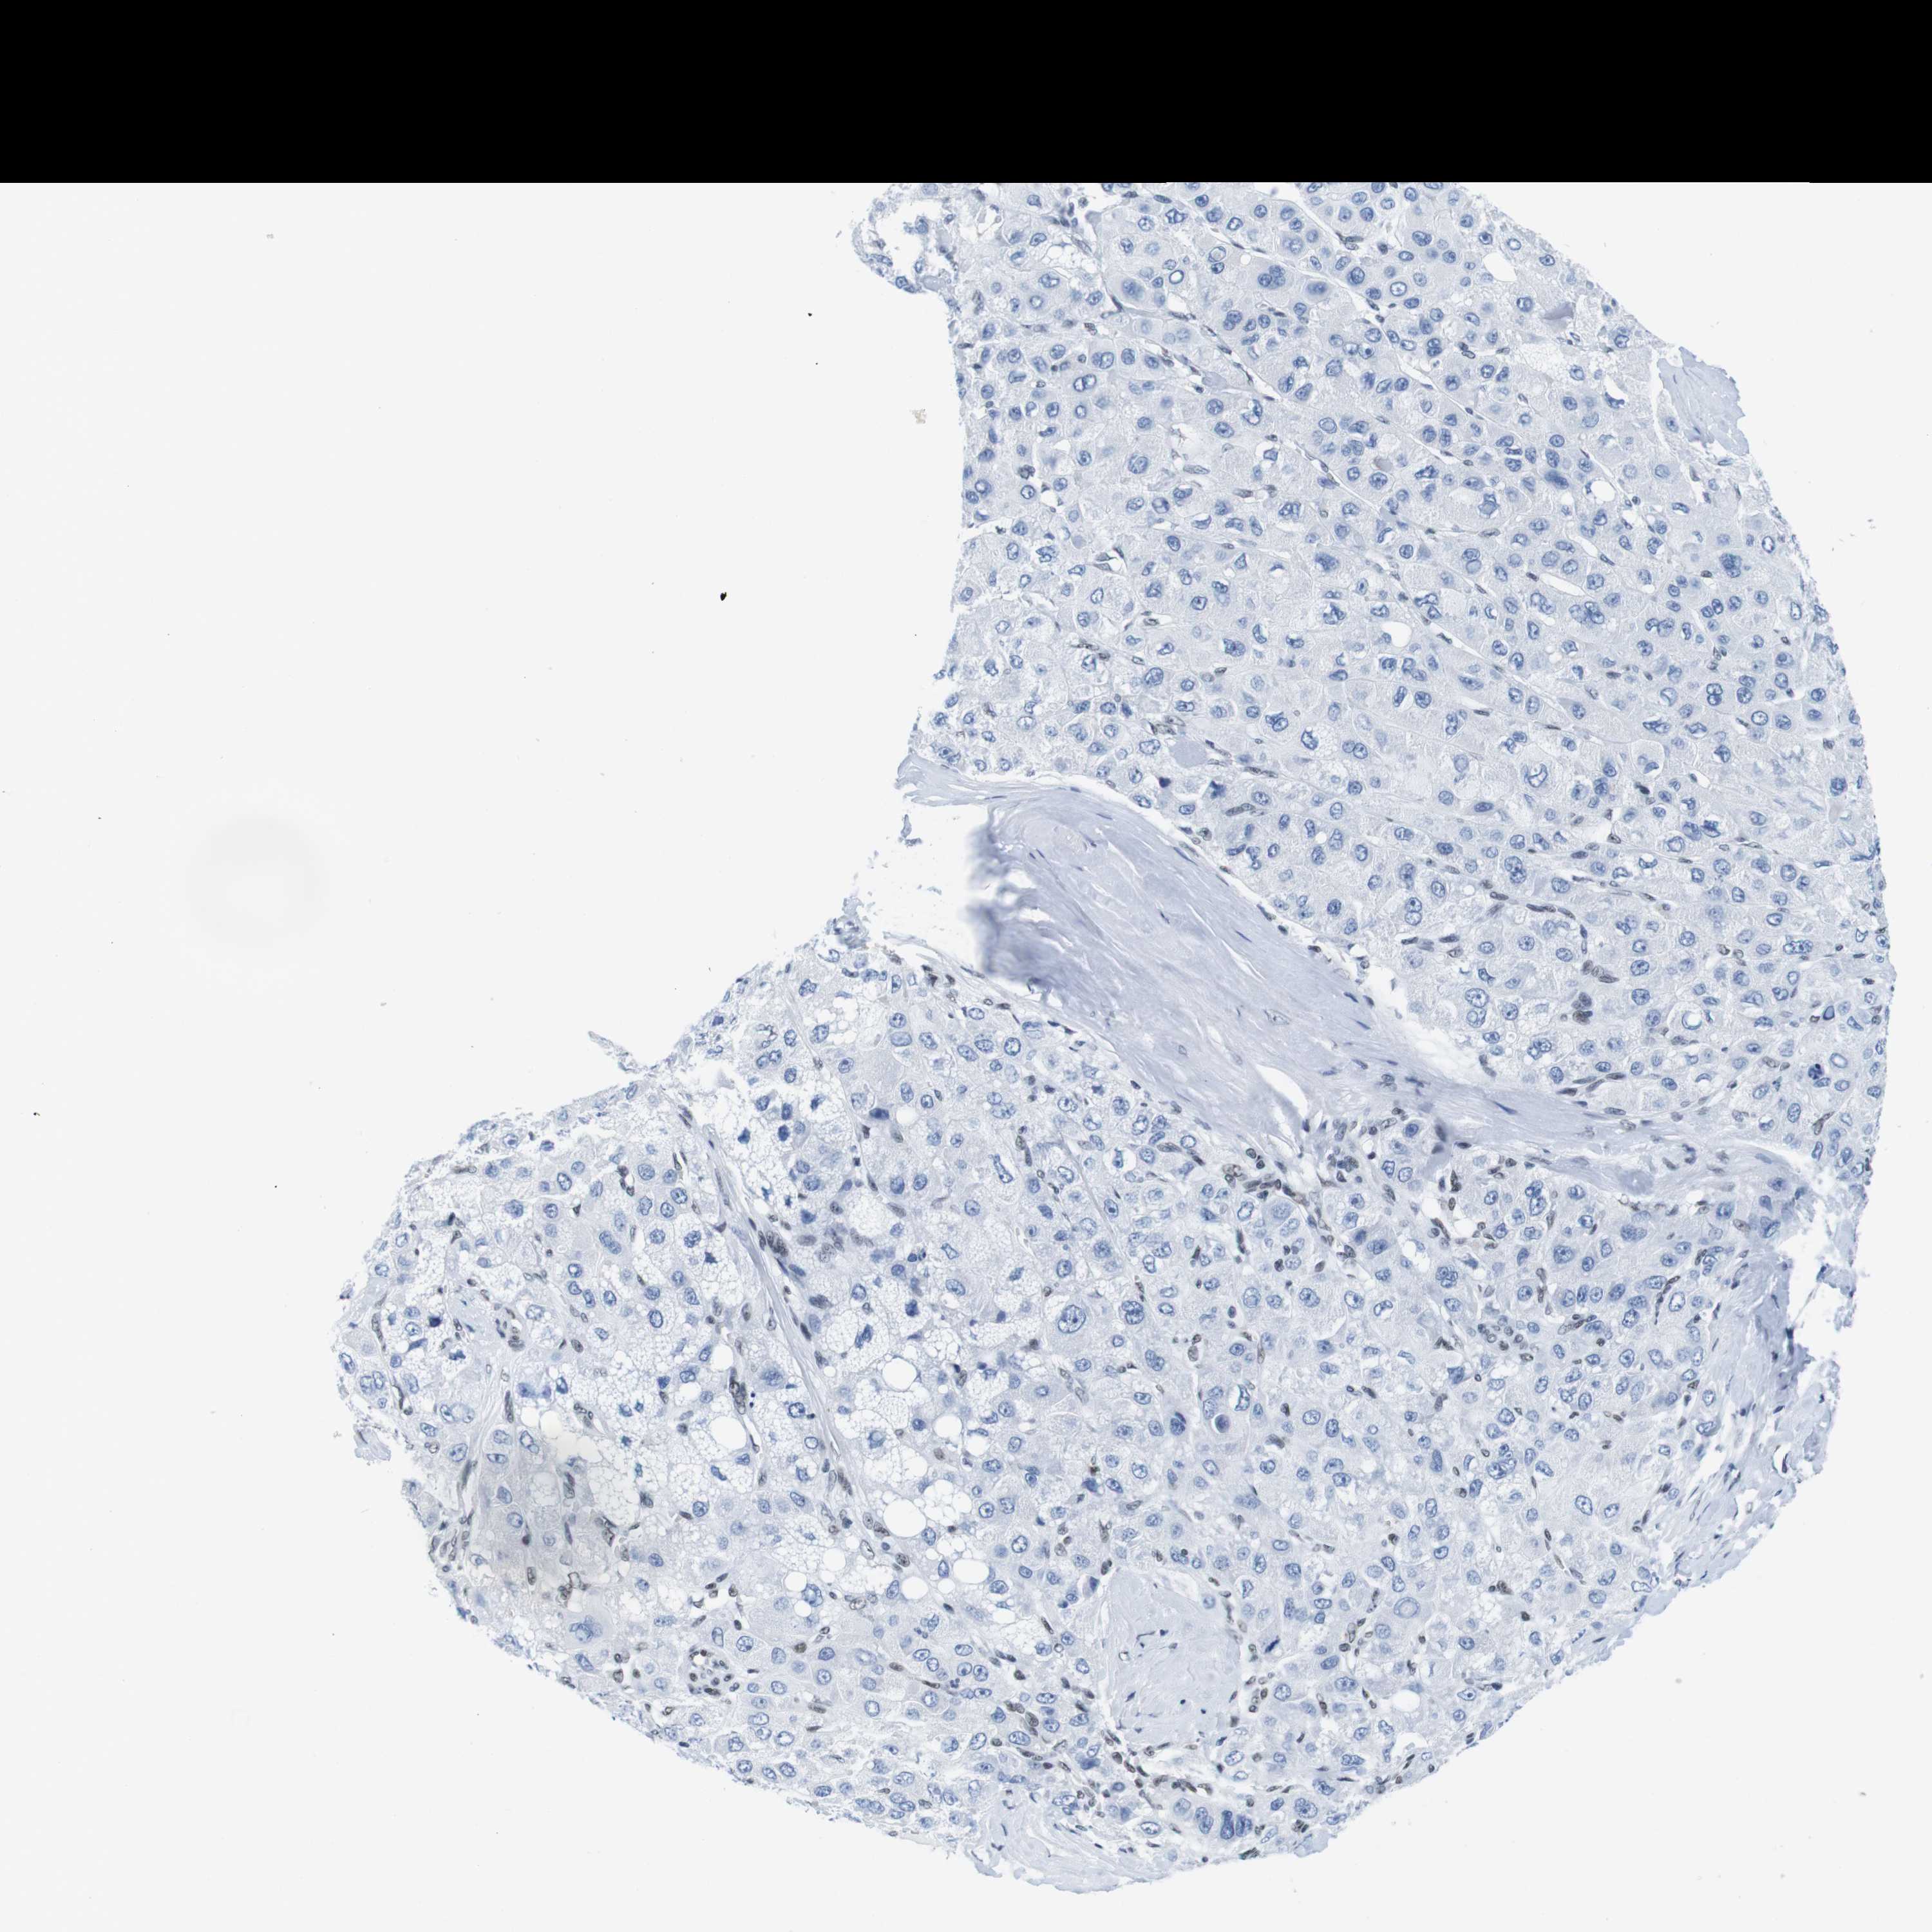

LIVER CANCER - Protein expressioni

A mouse-over function shows sample information and annotation data. Click on an image to view it in a full screen mode. Samples can be filtered based on level of antibody staining by selecting one or several of the following categories: high, medium, low and not detected. The assay and annotation is described here.

Note that samples used for immunohistochemistry by the Human Protein Atlas do not correspond to samples in the TCGA dataset.

Antibody stainingi

Antibody staining in the annotated cell types in the current human tissue is reported as not detected, low, medium, or high, based on conventional immunohistochemistry profiling in selected tissues. This score is based on the combination of the staining intensity and fraction of stained cells.

Each image is clickable and will lead to virtual microscopy that enables deeper exploration of all samples and also displays staining intensity scores, fraction scores and subcellular localization as well as patient and tissue information for each sample.

Antibody HPA002134

Antibody CAB016293

Staining

High

Medium

Low

Not detected

Intensity

Strong

Moderate

Weak

Negative

Quantity

>75%

75%-25%

<25%

None

Location

Nuclear

Cytoplasmic/membranous

Cytoplasmic/membranous,nuclear

Cholangiocarcinoma

Carcinoma, Hepatocellular, NOS